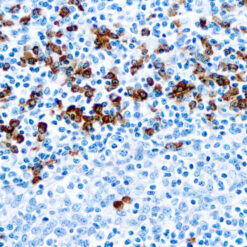

Cytokeratin (CAM5.2)

Anti-Cytokeratin (CAM 5.2) reagent has a primary reactivity with human keratin proteins that correspond to Moll’s peptides #7 and #8, Mr 48 and 52 kilodaltons (kd), respectively. Cytokeratin 7 and 8 are present on secretory epithelia of normal human tissue but not onstratified squamous epithelium. Anti-Cytokeratin (CAM 5.2) stains most epithelial-derived tissue, including liver, renal tubular epithelium, and hepatocellular and renal cell carcinomas. Anti-Cytokeratin (CAM 5.2) might not react with some squamous cell carcinomas.

| Positive Control Tissue | Colon, Lung, prostate and breast tissue. |